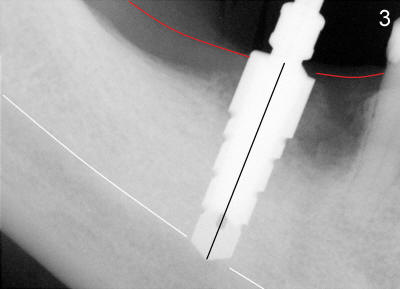

Mr. Chan is 58 years old and otherwise healthy.  Three months ago, the tooth #30 was extracted due to vertical root fracture.  He returned for implant placement.  A pre-op PA was taken without measuring the bone height before surgery. The measurement of bone height (white line in Fig.1) from the ridge of the septum to the upper border of the inferior alveolar canal (IAC, yellow dashed line) was done postop.  In fact, it is 17 mm.  Effort was exerted to make osteotomy in the septum and parallel to the long axis of the tooth #29.  When 2.5x17 tapered drill reached the depth, the patient felt pain.  PA was taken (Fig.2).  This time the invasion of IAC was overlooked again from the X-ray (Fig.2 white line).  The black line indicates the length of the drill (17 mm).  So far local infiltration had been used.  It was thought that pain was due to incomplete anesthesia.  After inferior alveolar nerve block, osteotomy was finished until 6x17 mm with combined bone expansion with Tatum osteotomes and drilling (Fig.3).  The invasion of IAC was obvious.  The base of the osteotomy was soft (probed with a thin curet) and the depth is more than 17 mm (explorer).  Tatum tapered implant (6x17 mm) was placed 2-3 mm short of osteotomy depth (Fig.4).  The tapered implant is originally designed to be placed supragingivally.